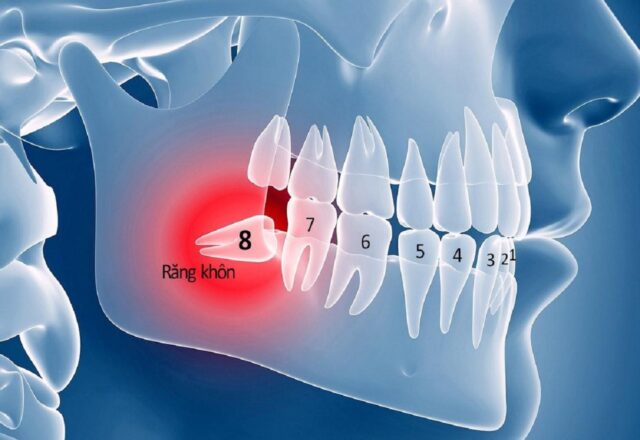

Răng số 8, hay còn gọi là răng khôn, luôn là chủ đề gây nhiều băn khoăn cho mọi người, đặc biệt là khi chúng có xu hướng mọc lệch, mọc ngầm. Một chiếc răng 8 mọc ngầm không chỉ gây đau đớn, khó chịu mà còn tiềm ẩn nhiều nguy cơ ảnh hưởng đến sức khỏe răng miệng và cả sức khỏe tổng thể.

Răng khôn là chiếc răng cuối cùng mọc trên cung hàm của mỗi người. Chúng nằm ở vị trí trong cùng, sau răng số 7 (răng hàm lớn thứ hai).

- Thời điểm mọc: Răng số 8 thường xuất hiện trong độ tuổi từ 17 đến 25, giai đoạn con người đã trưởng thành và được xem là “khôn” hơn, do đó mới có tên gọi là răng khôn.

- Cung hàm không đủ chỗ: Đây là nguyên nhân phổ biến nhất. Khi răng số 8 bắt đầu mọc, toàn bộ các răng khác trên cung hàm đã ổn định vị trí. Nếu xương hàm của bạn có kích thước nhỏ hoặc các răng khác quá lớn, không còn đủ khoảng trống, răng khôn buộc phải tìm đường mọc theo hướng bất thường, dẫn đến mọc nghiêng, mọc lệch hoặc mọc kẹt, mọc ngầm hoàn toàn dưới nướu và xương hàm.

- Sự cản trở từ răng số 7: Răng 8 mọc ngầm thường gặp sự cản trở từ chân hoặc thân răng số 7 ở phía trước, khiến nó không thể trồi lên đúng vị trí thẳng đứng.